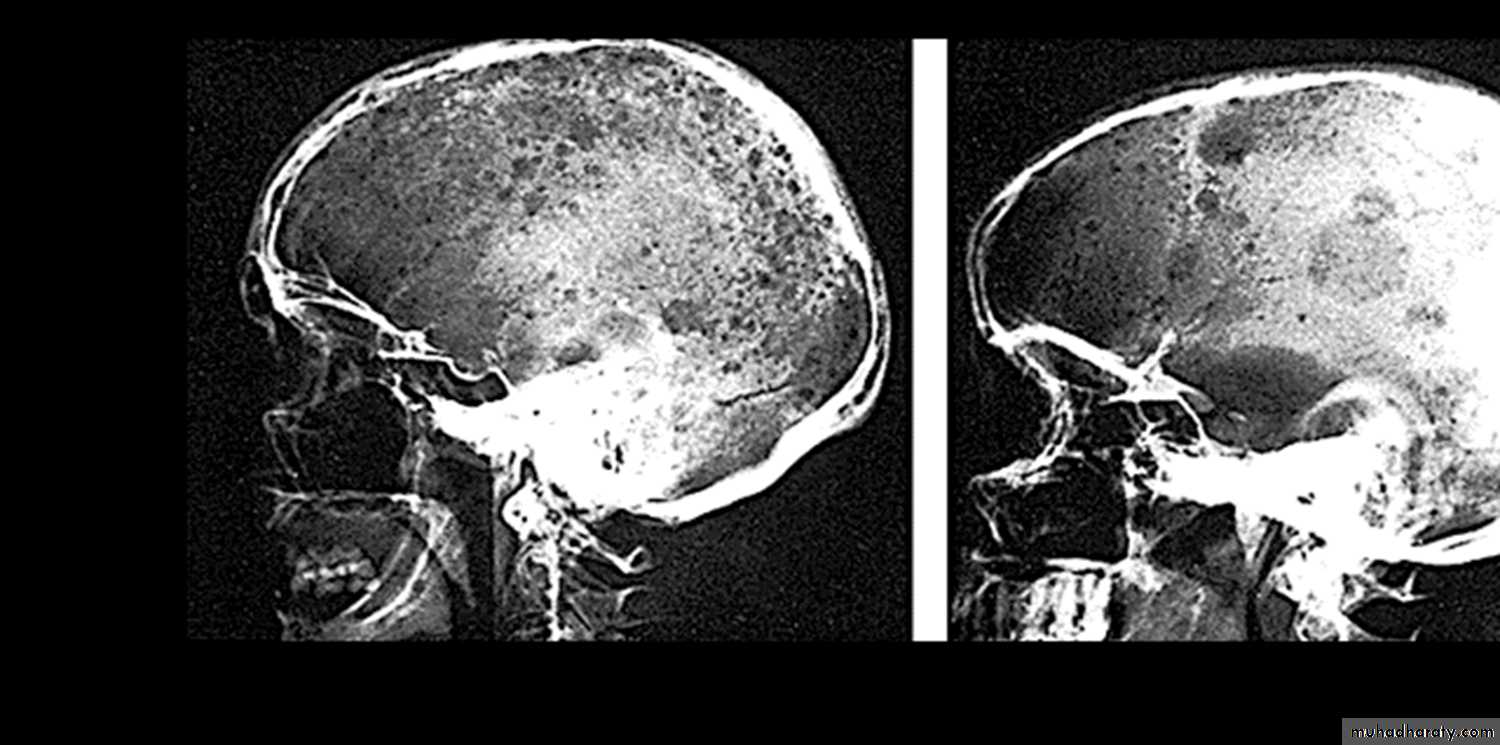

Multiple myeloma1. BM infiltration by Plasma cells. 2. Skull X-ray shows multiple osteolytic lesionPractical Examination in Pathology